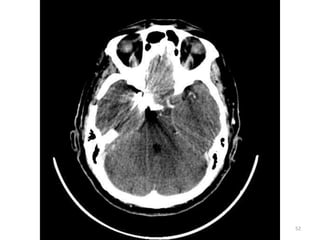

1. Medula espinal

(forame magnum)

2. Células mastóideas.

3. Seio maxilar esq.

4. Côndilo

mandibular(cabeça).

5. Processos zigomáticos.

6. Maxilar.

7. Osso nasal.